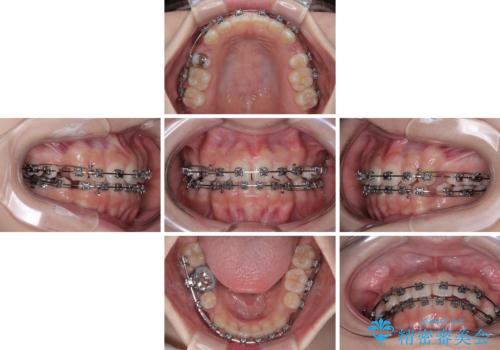

【モニター】デコボコとクロスバイトの前歯 ワイヤー装置での抜歯矯正

- 20代女性

- 矯正装置

- メタルブラケット

- 治療期間

- 2年2ヶ月

しかしながら、唇を閉じたときに口元に緊張感があり、そのまま叢生を解消すると横顔が突出した印象になる可能性が高かったため、上下左右の小臼歯4本を抜歯して、ワイヤー装置にて矯正治療を行うこととしました。

矯正治療後には、目立っていた奥歯の銀歯をオールセラミッククラウンへ作り替え、スッキリした口元に仕上がりました。